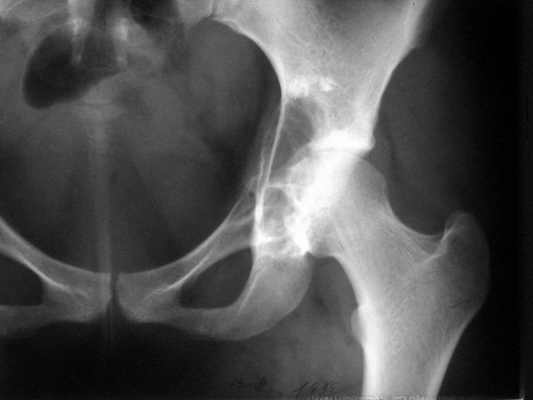

Женщина 22 лет поступила с протрузией вертлужной впадины.Рентгенограммы (1, 2) с интервалом в 1 год. В онкодиспансере сделали биопсию - ОБК без малигнизации. Какой объем операции здесь следует предпринять? Есть ли какие-то шансы на первичное эндопротезирование? Где такие операции делают? В том числе в Европе. Заранее спасибо.

The xray appearance is consistent with a bengin aggessive or malignant lesion involving both the acetablum and the femoral epiphysis (there appears to be erosions of the femoral head). The differential diagnosis would include non-tumor conditions such as Brown's tumor (a serum calcium should be measured), benign aggressive lesions such as GCT, ABC and chondroblastoma, and malignant lesions such as telangiectatic osteosarcoma and MFH of bone.

Заключение доцента Рыкова А.Г.:

1 .Большое сомнение в правильности гистологического заключения.

2. Впечатление о злокачественном процессе в костях таза.

3. Разговор не о первичном протезировании, а о радикальной операции.